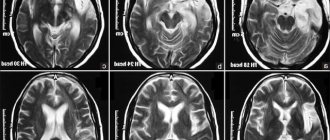

Ultrasound not only reveals the presence of a tumor, but also assesses the general condition of the brain, its blood circulation and disorders that are already present at the research stage. To clarify the diagnosis, diagnostic methods such as CT or MRI can be used.

MRI

Magnetic resonance imaging is the most informative method for diagnosing neoplasms affecting brain structures.

Thanks to the possibility of layer-by-layer scanning, a specialist can determine the structure and location of the cyst. But the method is used only for children aged 5 years and older.